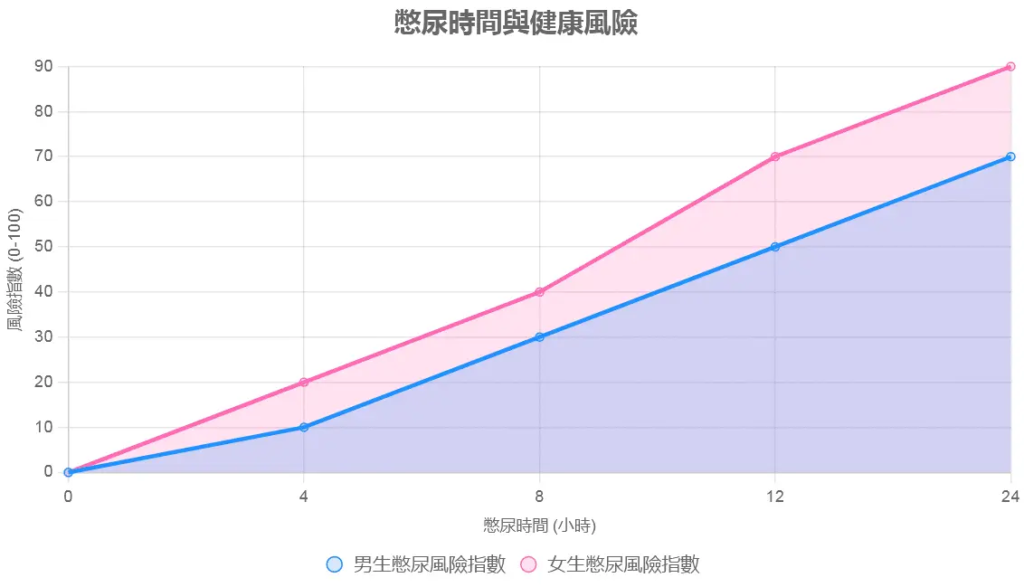

時間段:憋尿風險時間線

- 0-4小時:無礙,僅不適。

- 4-8小時:痛楚、感染風險增。

- 8-24小時:膀胱伸張,腎壓增。

- 24小時以上:破裂風險,死亡率<1%但存在。

憋尿風險時間線

描述:

此折線圖展示憋尿時間(小時)與健康風險(以風險指數0-100表示)的關係,比較男女風險差異:

- 男生曲線(藍色):0-4小時風險0-10(僅不適),4-8小時10-30(感染風險增),8-24小時30-70(膀胱伸張),24小時以上70-100(破裂風險)。

- 女生曲線(粉紅色):風險上升更快,4-8小時20-40,8-24小時50-90,因肌力較弱,膀胱耐受力低。

原因分析:

圖表顯示,女生因肌力與尿道結構,憋尿8小時後風險急劇上升。24小時以上,膀胱破裂風險(雖<1%)對女生更高,因膀胱壁耐受力較低。